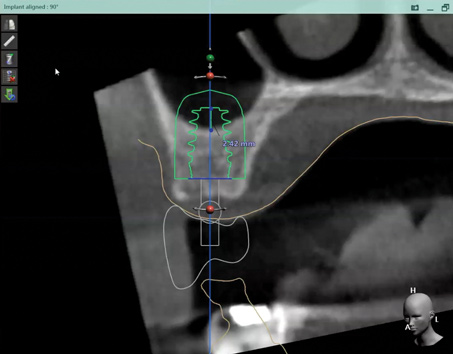

Fig 2. CBCT images show axial (Fig 2) and cross-sectional (Fig 3) views, and 3D reconstruction view (Fig 4) with virtually planned implant Nos. 8 and 9.

Figure 2

Fig 3. CBCT images show axial (Fig 2) and cross-sectional (Fig 3) views, and 3D reconstruction view (Fig 4) with virtually planned implant Nos. 8 and 9.

Figure 3

Fig 4. CBCT images show axial (Fig 2) and cross-sectional (Fig 3) views, and 3D reconstruction view (Fig 4) with virtually planned implant Nos. 8 and 9.

Figure 4